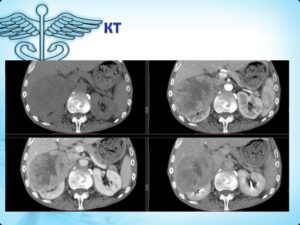

Одним из наиболее эффективных обследований считается компьютерная томография. Нарост на КТ изображается в виде гиподенсного образования, имеющего более низкую плотность, чем при непораженном органе. Кроме этого используют следующие методы исследования: